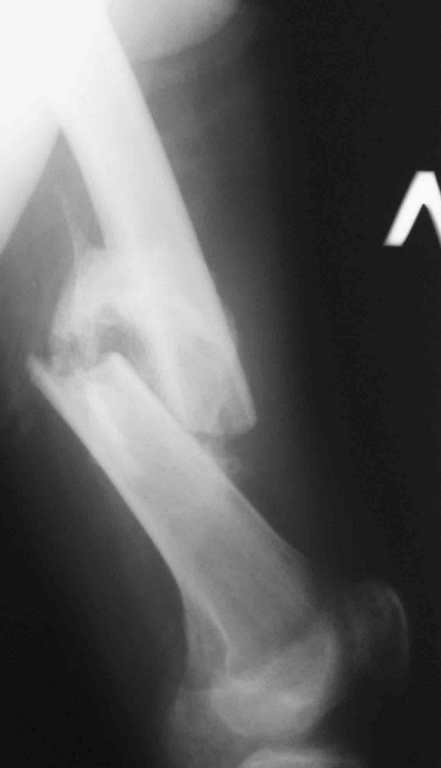

Re: 32- летний пациент с переломами обоих бедер после неудачного оперативного и консервативного лечения.

Иллюстрации к сообщению

Уважаемый Антон.Исходя из Вашего материального положения!! и наличия хорошего, грубого омозоления, равности длины конечностей и судя по снимкам не очень выраженной антекурвации, но выраженной контрактуры коленных суставов: чтоб не упустить время разработки суставов и активизировать больного, необходимо справа удалить стержень, рассверлить канал и произвести ЗИМО более толстым неблокир. стержнем т.к. на этом уровне можно получить устойчивый остеосинтез, после чего активизировать и дозированная, упорная ЛФК, а дальше после восстановления функции ,время покажеть.

Cyдя по представленным рентгенограммам оба бедра консолидированы. Необходима активная разработка движений в коленных суставах. Хотелось бы увидеть фотоснимки больного ( нижних конечностей спереди и сбоку). Если стержень мешает разработке движений то его надо удалить.

О происхождении такого запущенного случая- мой коллега работает экспертом ВТЭК и тянет в отделении и не такие казусы. Сегодня была сделана операция удален стержень из бедра и установлен стержневой аппарат из 2 опор, слева подвижности не наблюдалось, продолжается ЛФК. При необходимости позднее будет выполнена надмыщелковая корригирующая остеотомия. Спасибо всем за советы.